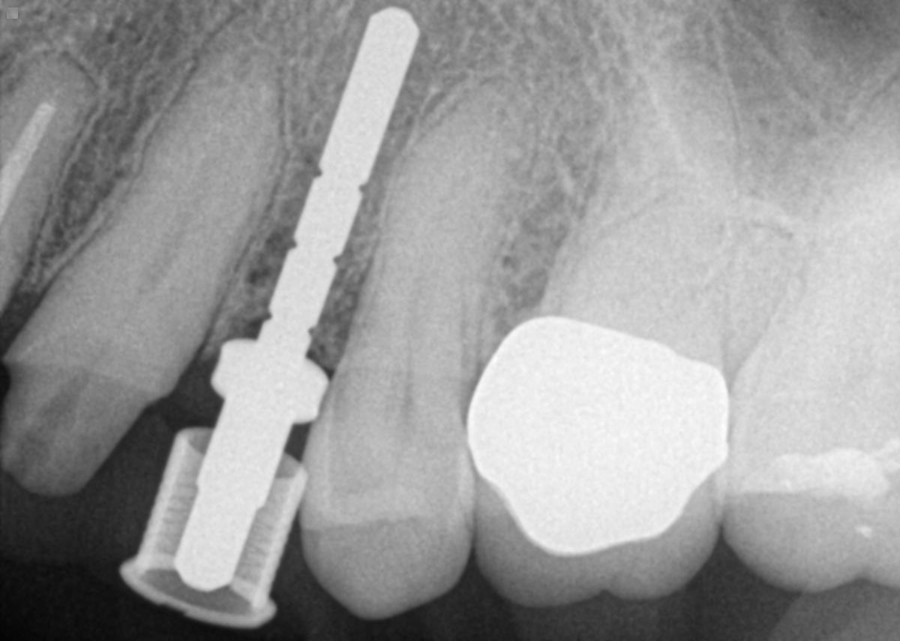

4. After surgery, several X-rays were taken to verify implant placement. Figure 7 shows accuracy to the guided placement for the implant in tooth #12 position (which mirrors the planning stage of Figure 4). Figure 8 shows the implant in tooth #8 position with healing abutment. Figure 9 shows the placement of the implant for tooth #5.

Fig. 7 Fig. 8